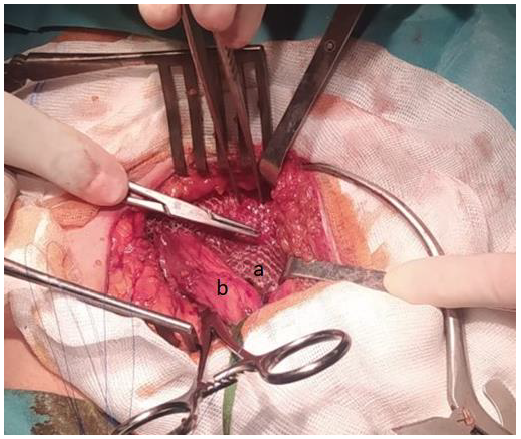

His right IH was treated by open Lichtenstein TFMH (Figure 2), and PD was resumed 4 weeks after the operation. Currently, after 12 months of follow-up, the patient remains recurrence-free while on CAPD due to his preference.

Figure 2.Figure 2. Hernioplasty according to the Lichtenstein technique. a: Polypropylene mesh, b: Spermatic cord